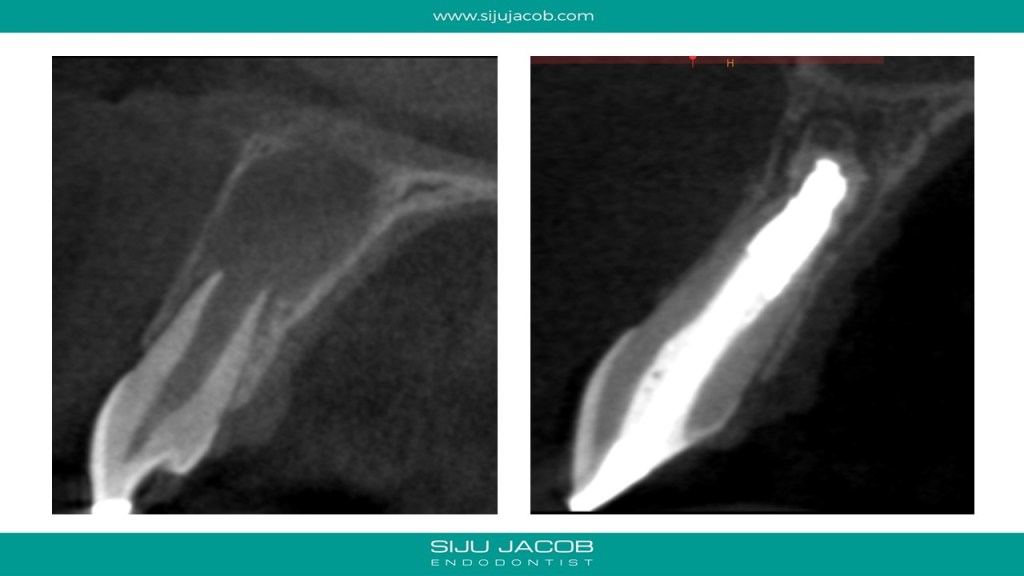

This was probably the largest lesion I ever treated. It had several interesting characteristics. It would be tough to explain with just pics. So, I made it into a short presentation